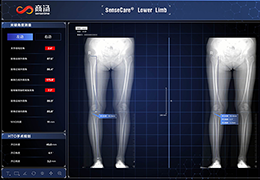

工作流智能。

在这里,先进的智能功能自动执行手动任务和工作流程步骤,以简化流程,提高技术人员工作效率,节省时间和金钱,并增强患者护理。

自动化设备定位和患者姿势确认可优化放射科技师的效率并加快工作流程。

自动技术选择可改善影像一致性并支持辐射剂量控制。